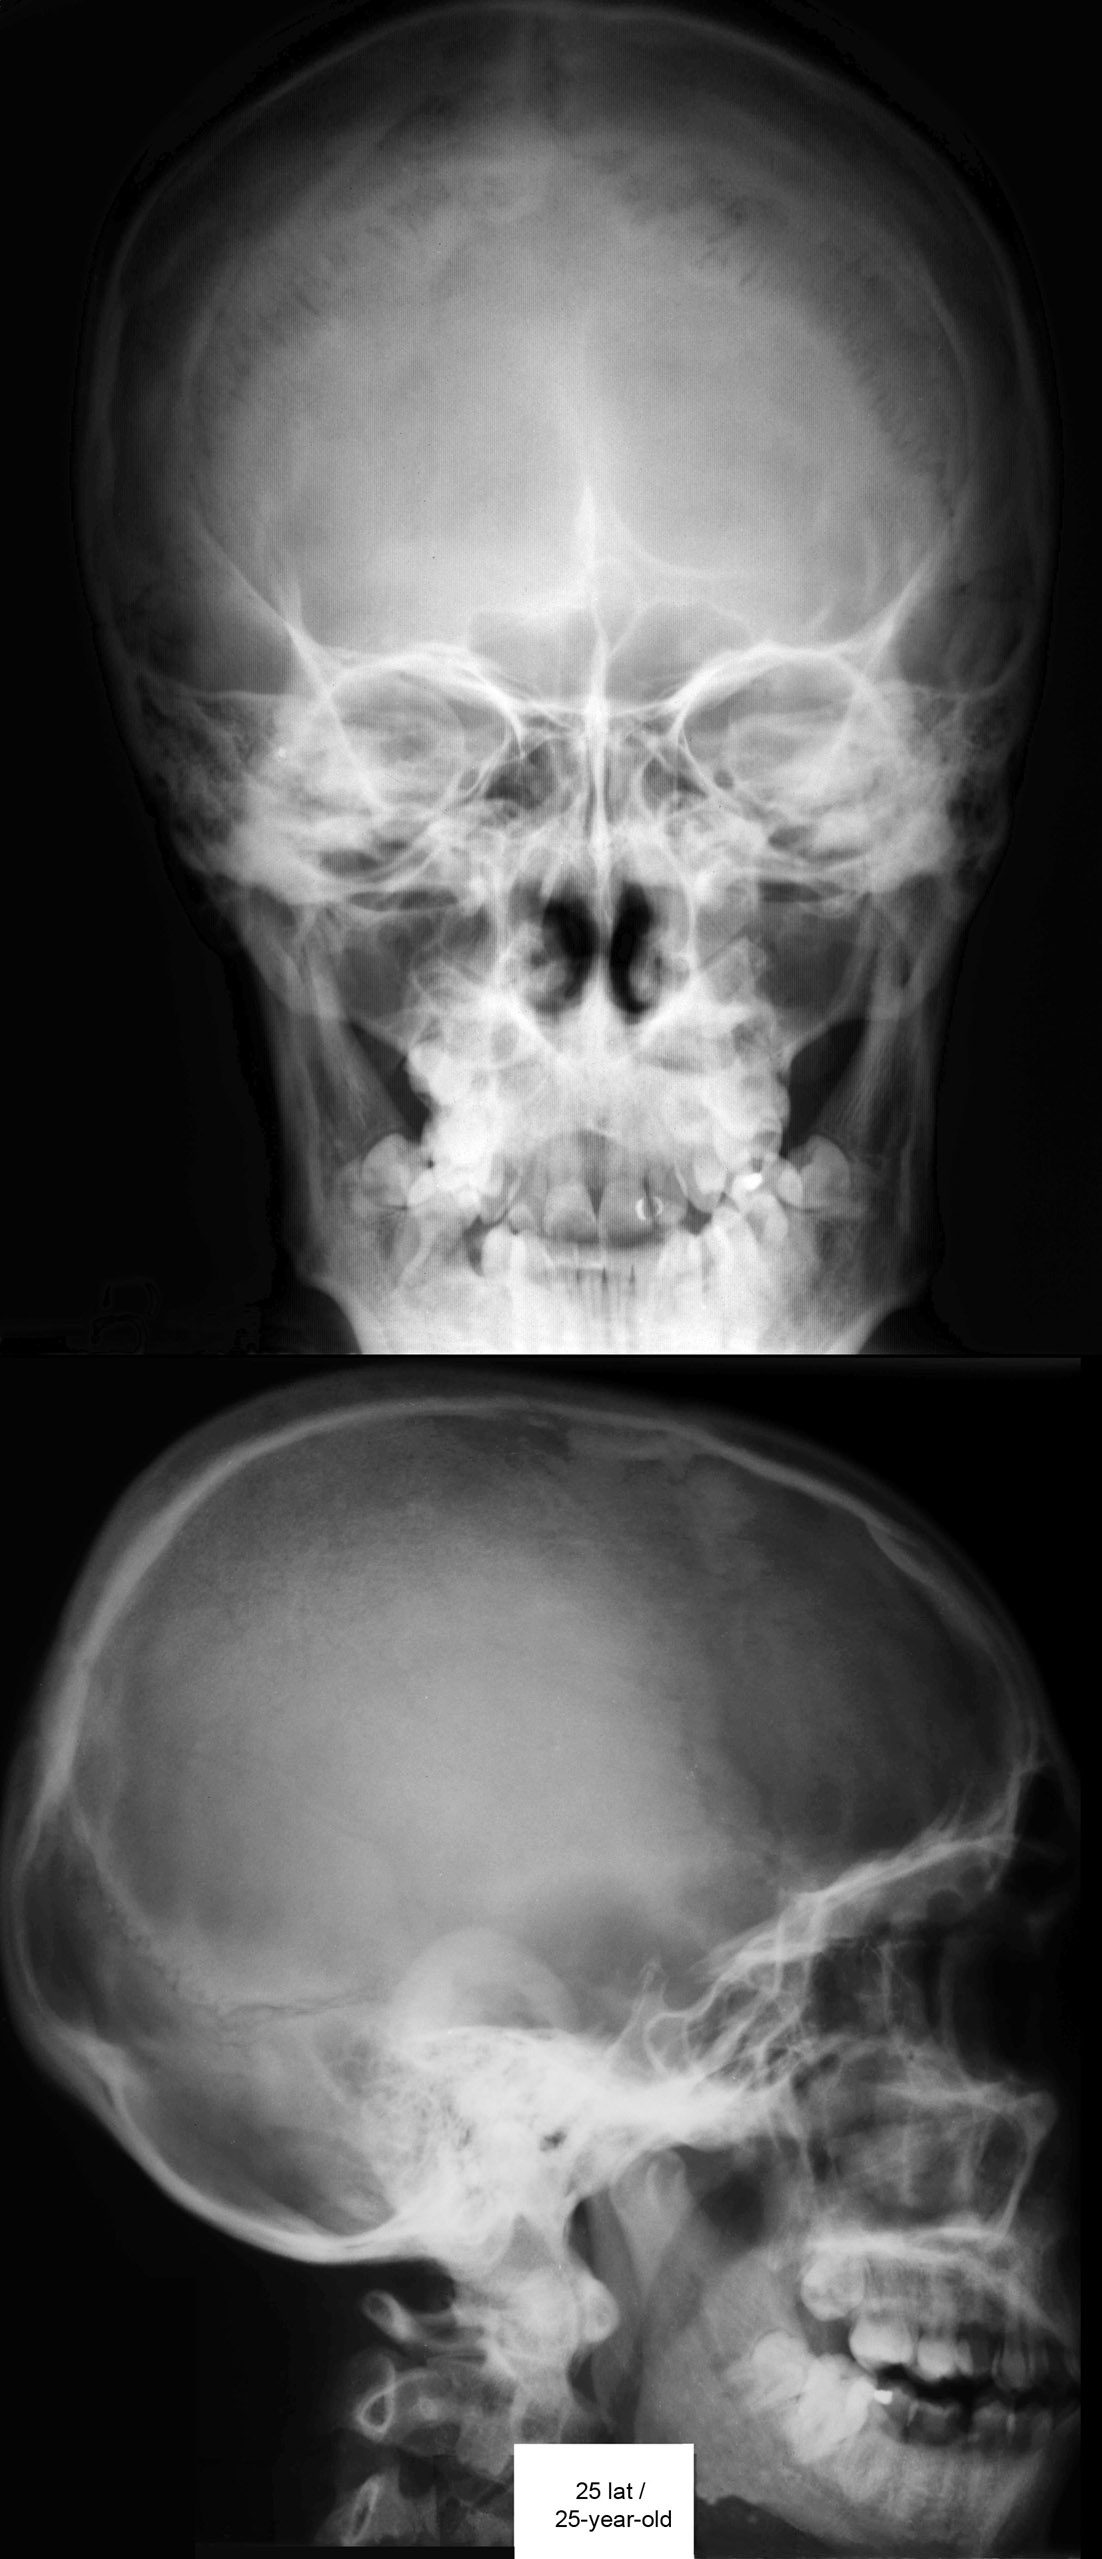

Radiografia / Radiography

RTG głowy 25-latka.

. RTG głowy 14-, 25- i 70-latka.

RTG głowy frontalny.

RTG głowy boczny.